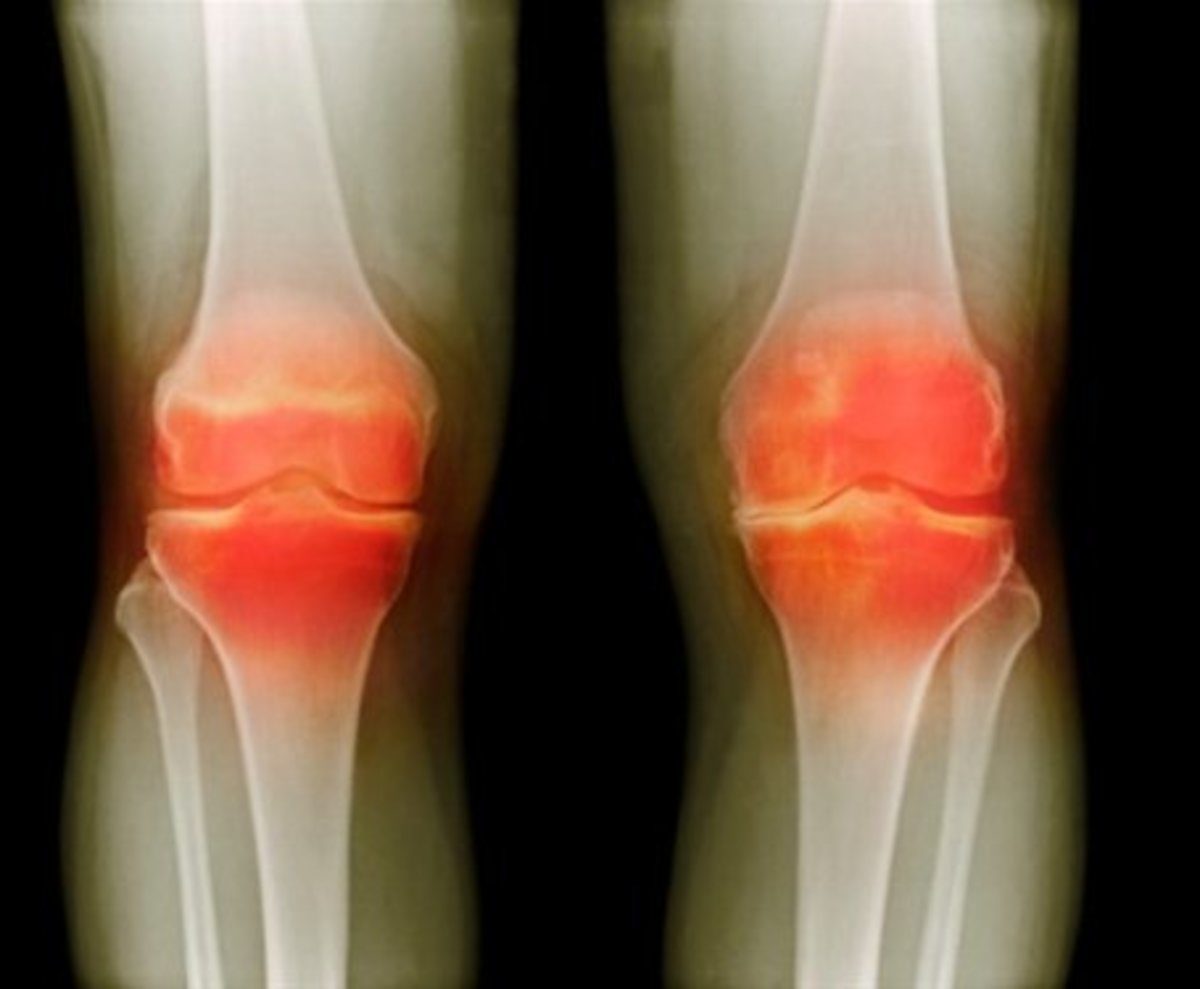

Παρά το γεγονός ότι κάθε άρθρωση μπορεί να επηρεαστεί, συνήθως η σηπτική αρθρίτιδα εμφανίζεται στους ενήλικες στο γόνατο και στο ισχίο στα παιδιά.